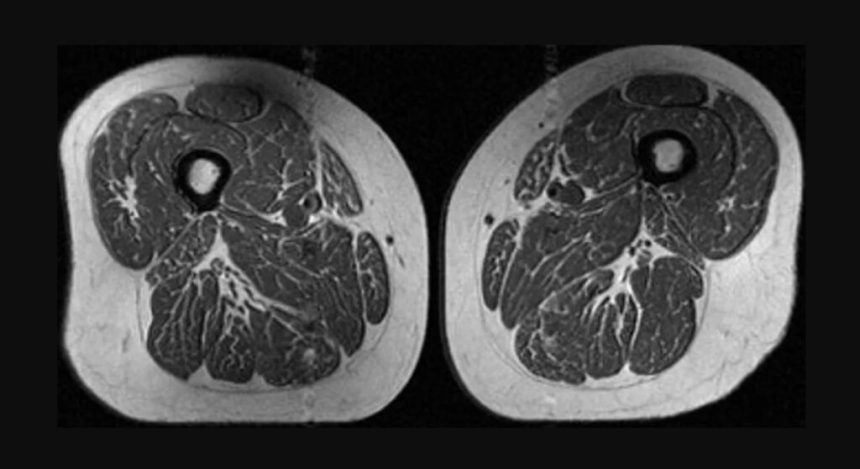

Un studiu recent, bazat pe scanări RMN efectuate pe peste 600 de persoane, a dezvăluit o legătură semnificativă între consumul de alimente ultraprocesate și creșterea grăsimii intramusculare. Imaginile obținute au arătat mușchi cu aspectul unei „fripturi marmorate”, datorită stratelor subțiri de grăsime infiltrate printre fibrele musculare. Această descoperire alarmantă sugerează că degradarea calității musculare poate începe înainte de apariția simptomelor vizibile, conform CNN.

Efectele negative ale grăsimii infiltrate asupra mușchilor includ reducerea capacității de regenerare și scăderea forței musculare. Pe termen lung, acest proces poate contribui la dezvoltarea unor afecțiuni precum osteoartrita genunchiului. De exemplu, mușchii coapselor sunt cruciali pentru menținerea stabilității articulațiilor, iar slăbirea lor poate crește presiunea asupra genunchilor, mai ales în cazul persoanelor supraponderale. Experții avertizează că această degradare nu se limitează la o singură zonă a corpului, ci poate afecta mai multe grupe musculare, indicând un proces sistemic.

Studiul a subliniat că grăsimea infiltrată în mușchi poate afecta serios capacitatea acestora de a se regenera, având un impact negativ asupra forței musculare. De asemenea, s-a constatat că această problemă poate apărea chiar și la persoane fără semne evidente de osteoartrită, indicând o degradare musculară prezentă înainte de manifestarea simptomelor clinice.